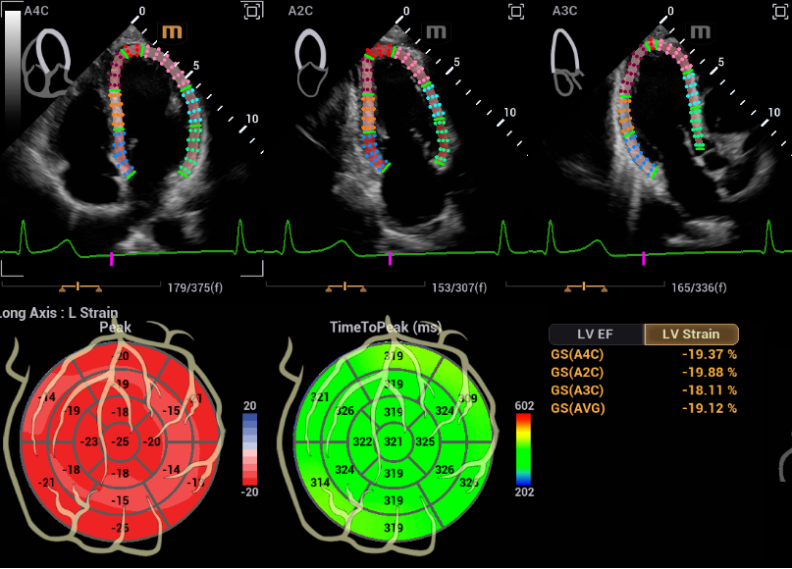

心血管超声诊断系统鲲鹏 Recho R9具有更清晰的心血管影像,更精准的心功能评估

和更高效的工作体验。

鲲鹏将具备Auto Strain自动应变评估技术,智能化切面识别并追踪室壁运动,高效评估心肌运动状况;还有Auto EF 自动射血分数测量,自动识别心动周期并描迹心内膜边界,计算左室心功能测量参数,评估心脏收缩功能。

骨盆手术器械有哪些2023十大自主创新医疗器械产品_https://www.jmylbn.com_新闻资讯_第33张

Auto Strain自动应变评估技术